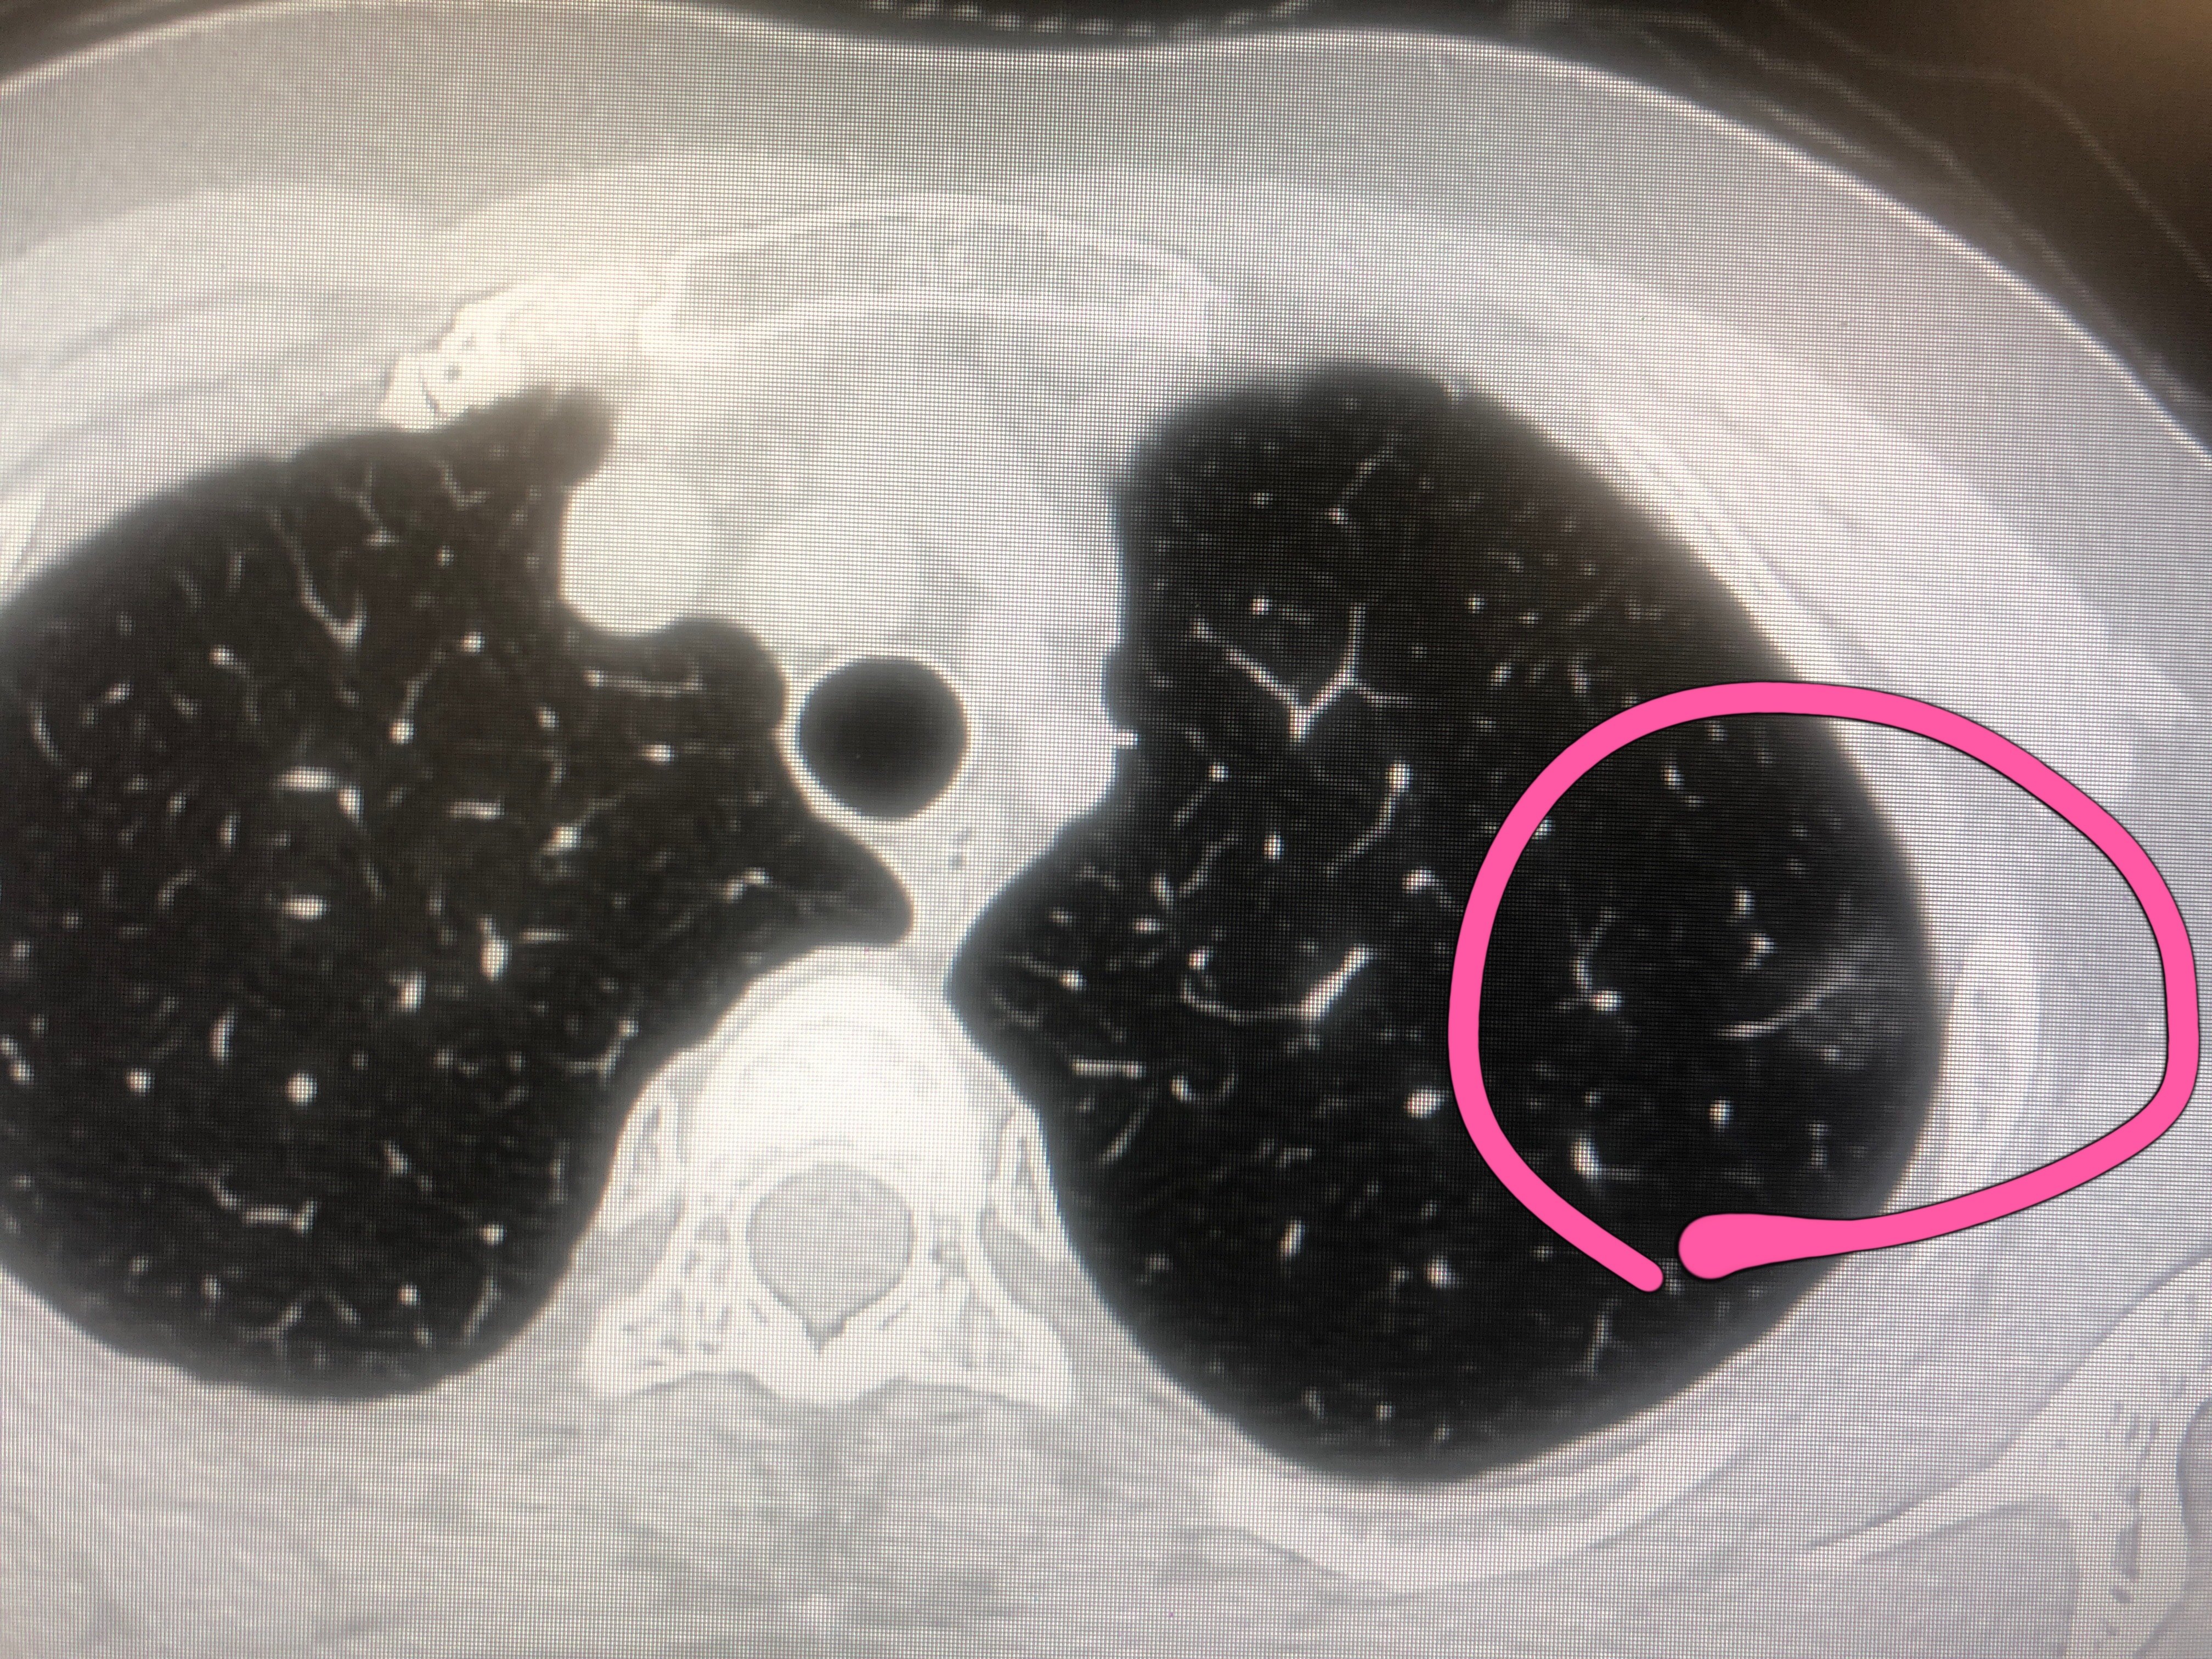

磨玻璃结节(ground-glassnodule, GGN)是肺内有局灶性云雾状密度增高影,包括边界清楚和不清的病变,但能显示出其中的血管和支气管纹理,这一典型的胸部CT影像称为磨玻璃结节,就像在肺组织上蒙了一块磨玻璃一样。病理表现为肺泡壁增厚,肺泡腔塌陷,含气量减少,出现细胞、渗出液及组织碎片。根据是否含实性成分,将GGN分为纯磨玻璃结节(pGGN)和伴有实性成分的混合磨玻璃结节(mGGN)。

CT是显示GGN的首选方法。对于GGN良恶性的鉴别,需要根据结节的大小、形态、边缘及瘤-肺界面,结节内部密度特征,内部结构特征,瘤周结构以及病灶随访观察等表现综合分析做出正确的诊断和鉴别。

随着结节体积增大,GGN的恶性或浸润性概率增加;大多数恶性GGN的整体形态为圆形或类圆形,结节边缘多呈分叶状,或有毛刺征(又称棘状突起),结节边缘清楚但不整齐,瘤-肺界面清晰、毛糙甚至有毛刺。

GGN密度较高、不均匀提示恶性可能性大;持续存在的GGN大多数为恶性,或有恶性发展倾向。GGN的平均CT值对鉴别诊断具有重要价值,密度高恶性概率大,密度低恶性概率小,同时需要结合结节大小和形态变化来综合判断。